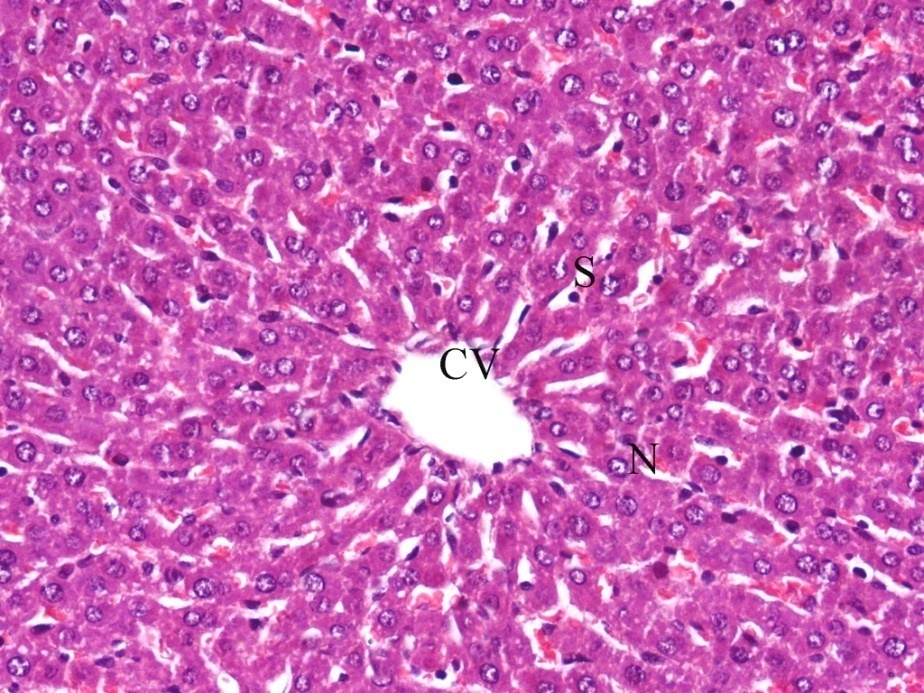

Normal structure of the hepatocytes, central vein, sinusoidal spaces and prominent nucleus were observed in the liver section of control rats (fig. 2). Cisplatin exposure caused marked damage to hepatocytes in the form of degeneration, cytoplasmic vacuolation, centrilobular necrosis associated with mononuclear cells infiltration around central vein and the central vein was enlarged and congested. The sinusoid walls showed numerous Kupffer cells, hemorrhages with sinusoids dilatation, and nuclei are pyknotic with condensed chromatin (fig. 3).

Fig. 2: It shows photomicrograph of section from liver of control group

Fig. 3: It shows photomicrograph of section from liver of cisplatin (H and E X 400)